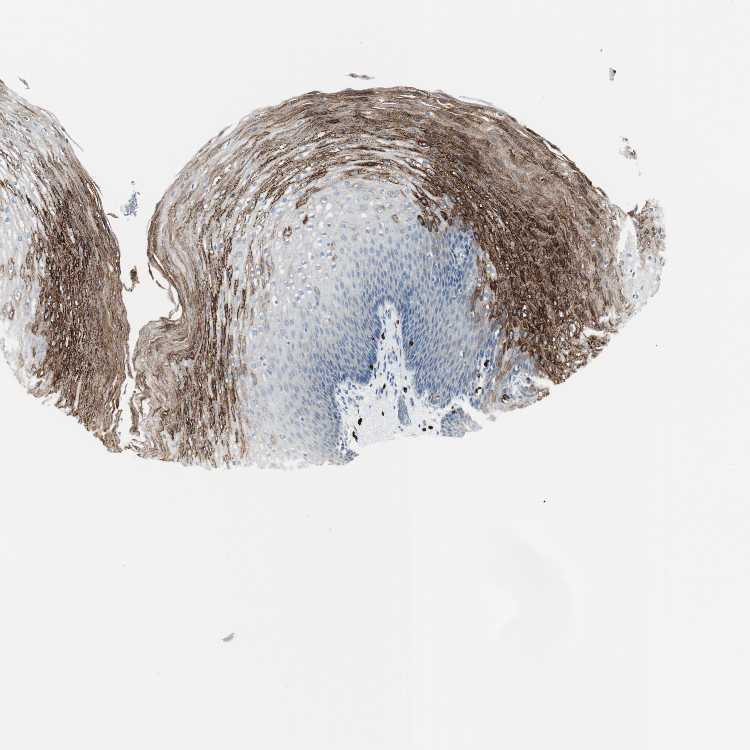

ESOPHAGUS - Antibody stainingi

Antibody staining in the annotated cell types in the current human tissue is reported as not detected, low, medium, or high, based on conventional immunohistochemistry profiling in selected tissues. This score is based on the combination of the staining intensity and fraction of stained cells.

Each image is clickable and will lead to virtual microscopy that enables deeper exploration of all samples and also displays staining intensity scores, fraction scores and subcellular localization as well as patient and tissue information for each sample.

Antibody HPA010122Antibody HPA071006Antibody CAB001999Antibody CAB002000

Squamous epithelial cells MediumNot detectedNot detectedLow